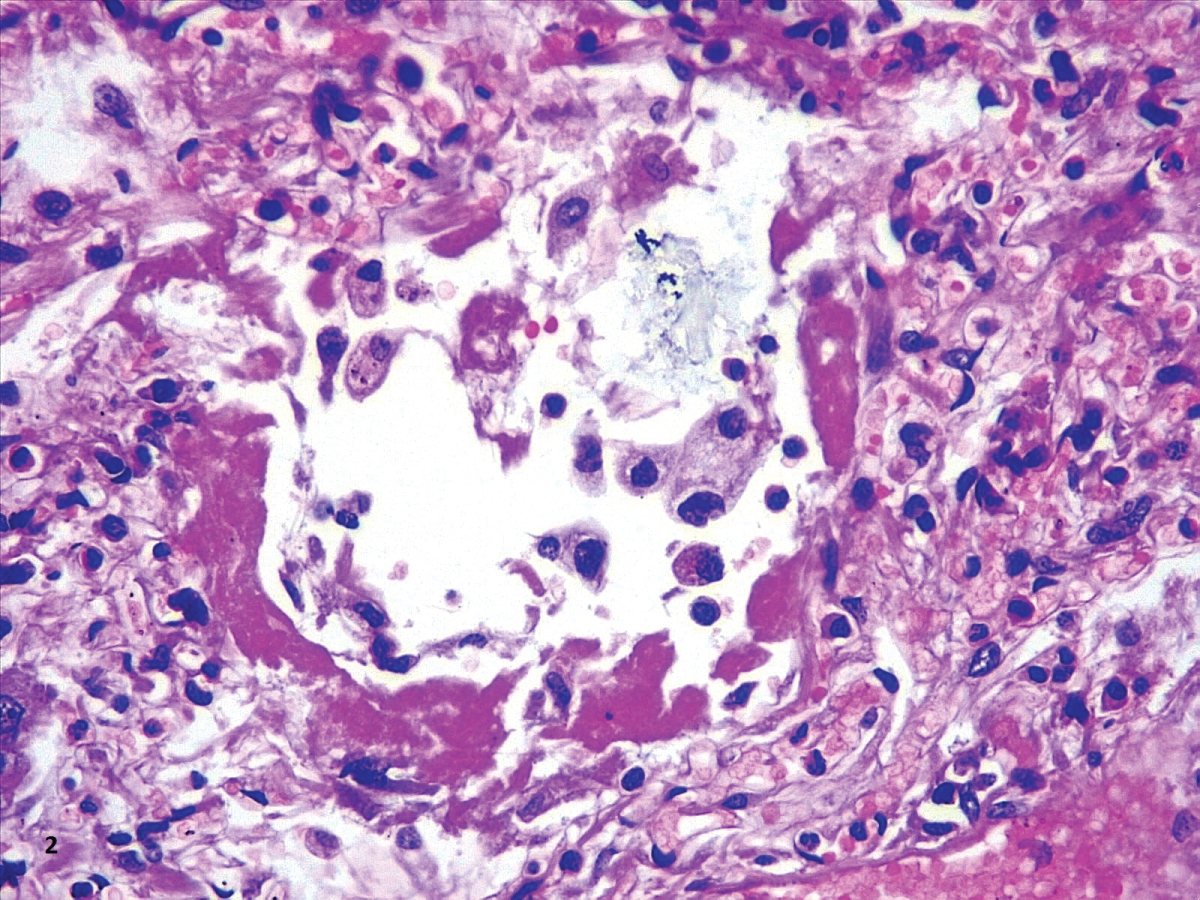

In our cases, we observed markedly congested vessels (Figure 1), and prominent DAD with coexistence of exudative and proliferative phases in most patients (Figure 2 and Figure 3). In the periphery of the more compromised areas, the presence of alveolar microthrombi was striking. The immunohistochemistry with TTF-1 highlighted the hyperplasia of atypical type II pneumocytes (Figure 4); and with CK7 collapsed alveoli were surrounded by a fibroblastic proliferation (Figure 5). As it was observed by others, we found scant inflammatory infiltrates in the majority of cases, but those complicated by bronchopneumonia (Figure 6). We also found giant multinucleated cells, which were positive to CK7, and had cytopathic-like changes in the majority of cases (Figure 7). The cytopathic-like changes consisted of large nuclei, nucleolar inclusions, lumpy chromatin, and a large, eosinophilic cytoplasm; however, these changes are not specific for Sars-cov-2, therefore they cannot be used as diagnostic criteria for COVID-19 pneumonia. Variable amounts of CD68 positive alveolar macrophages were identified (Figure 8). Interestingly, higher amounts of alveolar macrophages were observed in patients with the highest values of ferritin (observation not systematized). This finding correlates with the role of ferritin in macrophage activation and the proposal to include COVID-19 within the hyperferritinemic syndromes [38].

Figure 4: Hyaline membranes with atypical pneumocytes (HE,40X). View Figure 4